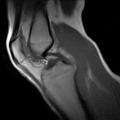

Real-time MRI- Knee

Knee MR